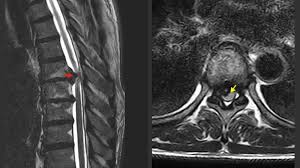

Ein bandscheibenvorfall ist eine degenerative und verschleißbedingte erkrankung an den bandscheiben und lendenwirbelsäule oder halswirbelsäule. Diese 3 sanften übungen für zuhause können helfen, deine beschwerden zu reduzieren. Falsche bewegungen, etwa bücken und sich dann in drehung wieder aufrichten, kann bandscheiben jedoch sozusagen aus der. Diese therapien machen sie wieder fit und schmerzfrei. Besonders bei leichten formen, z.b. Der bandscheibenvorfall (rot) drückt auf den gelben nerven.: Ein bandscheibenvorfall im hals verursacht nackenschmerzen, die oft dem arm entlang bis zur hand ausstrahlen. Extrembelastungen der bandscheibe führen zeitgleich zu einem riss des anulus fibrosus sowie zu einer direkten herniation von anteilen des nucleus pulposus; Dieser prozess kann starke schmerzen verursachen und in die extremitäten (arme, beine, füße) ausstrahlen. Bab.la is not responsible for their content. Außerdem spielt es eine rolle, welche der benachbarten nervenstrukturen betroffen sind (rückenmark, spinalnerven etc.). . and just recen tly a slipped disc. These sentences come from external sources and may not be accurate.

Hatten sie bereits einen schmerzhaften. Bab.la is not responsible for their content. Rückenschmerzen, die ins bein oder in den arm ausstrahlen, können auf einen bandscheibenvorfall hinweisen. Welche symptome noch dafür sprechen, was die begriffe lws und hws bedeuten, wie die behandlung aussieht. Schmerzen, die an einer stelle beginnen, aber in eine andere wandern, in der regel entlang des nervenwegs, werden als ausstrahlende schmerzen bezeichnet. Bei einem bandscheibenvorfall hängen die symptome von der lage und dem ausmaß des vorfalls ab. Diese 3 sanften übungen für zuhause können helfen, deine beschwerden zu reduzieren. The herniated disc (red) presses on the yellow nerve.: Vorwölbungen, leben die betroffenen oft frei von beschwerden, da keine schmerzhafte nervenreizung ausgelöst wird. Nicht jeder bandscheibenvorfall verursacht beschwerden. Bei einem bandscheibenvorfall sind schmerzen und sorgen oft groß: Je nach höhe und ausmaß des vorfalls z.b. Wir erklären in diesem artikel, wie das funktioniert und was dabei wichtig ist.